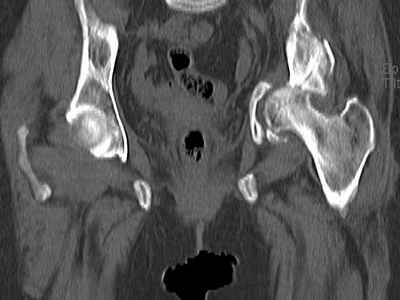

Уважаемые коллеги, возник вопрос по лечению нашей пациентки 60 лет. Около года назад множественная травма: в том числе Т-образный перелом вертлужной впадины. На сегодняшний день сращение отломков имеется на ограниченных участках, имеется дефект задней колонны вертлужной впадины. Движения неплохие, ходит с костылями, приступая на ногу. По мнению эдопротезистов при установке антипротрузионного кольца или октопуса не хватит костного материала и необходимо перед протезированием выполнить реконструкцию впадины, иначе чашка протеза неминуемо выпадет.Просьбы поделиться положительным и отрицательным опытом протезирования в подобных случаях.Возможно ли обойтись без реконструкции?Или лучше с ней?С уважением РАВ.

По моему мнению предварительну реконструкцию делать нет необходимости. Операцию надо выполнять одномоментно с пластикой вертлужной впадины. по поводу того, что не хватит головки. Да не исключено. Но ведь есть и другие материалы. Лучше при таком раскладе иметь в запасе замороженную головку. если нет возможности, как вариант два крыла подвздоной кости + хронос или его аналоги. По поводу выбора конструкции. Октопус в данной ситуации будет совсем не уместен, т.к. имеется дефект задней колонны вертлужной впадины. Да как конструкция октопус встанет не плохо. Но в функциональном плане не будет хорошей задне латерально и заднемедиальной точек опры впадины на период перестройки трансплатов. И по этому в данной ситуации более уместно кольцо Бурх(г)-Шнайдера с аналогичной пластикой, но возможнотью зафиксировать отломки задней колонны, крыши. Естественно цементная чашка с козырьком из кросс линк полиэтилена. Гололвка керамика, ножка бесцементная можно Цваймюллера или любой другой конструкции, они сейчас все хороши.

Исходя из своего опыта могу рекомендовать первичное протезирование пациентки.Костного материала из головки бедренной кости и крошки из шарошки должно хватить для заполнения дна вертлужной впадины.

Основное внимание необходимо уделить стабильности костных фрагментов в зоне перелома вертлужной впадины. Если имеется нестабильность я предпочел бы Октопус для остеосинтеза и стабильности вертлужной впадины. Этот момент является основным для успешного протезирования.

Если впадина единое гнездо по окружности, достаточно антипротрузионного кольца или Буршнайдера.